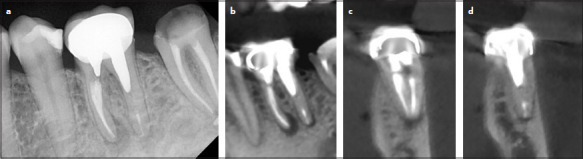

牙髓显微手术(Endodontic microsurgery, EMS)是一种针对传统根管治疗未愈合的感染牙根尖的特殊治疗方式。最近,使用先进的三维(3D)重建技术,如锥形束计算机断层扫描(CBCT),改善了牙科的诊断和治疗。然而,使用这种技术准确定位根尖可能具有挑战性。此外,传统的手术方法通常需要大量的骨切除,这通常会导致手术时间延长,并增加创伤和感染的风险。本文介绍了靶向EMS的概念,使用3d打印的手术指南和环钻来完成复杂病例的单步截骨和根尖切除。使用计算机辅助规划软件设计手术指南,以确保精确的角度和准备深度,同时避免关键解剖区域。环钻的使用使截骨术在位置、角度和准备深度方面变得有效和准确。本病例报告描述了使用3d打印指南和环钻来准确地执行下颌第一磨牙的EMS与分离的器械和根尖周围病变。(eej - 2024 - 03 - 043)。

Endodontic microsurgery (EMS) is a specific treatment modality that targets the root apex of infected teeth that have not been healed by traditional root canal treatments. Recently, the use of advanced three-dimensional (3D) reconstruction technology, such as cone beam computed tomography (CBCT), has improved diagnosis and treatment in dentistry. However, locating the root apex accurately using this technology can be challenging. Also, traditional surgical methods often require significant bone removal which usually results in prolonged surgery and increased risk of trauma and infection. This article introduces the concept of targeted EMS using the 3D-printed surgical guide and a trephine bur to perform single-step osteotomy and root-end resection in complex cases. The surgical guide was designed using a computer-aided planning software to ensure precise angulations and depths of preparation while avoiding critical anatomy regions. The use of the trephine bur enabled efficient and accurate targeted osteotomy regarding the site, angulation, and depth of preparation. This case report describes the use of the 3D-printed guide and the trephine bur to accurately perform EMS of a mandibular first molar with a separated instrument and periapical lesions. (EEJ-2024-03-043).